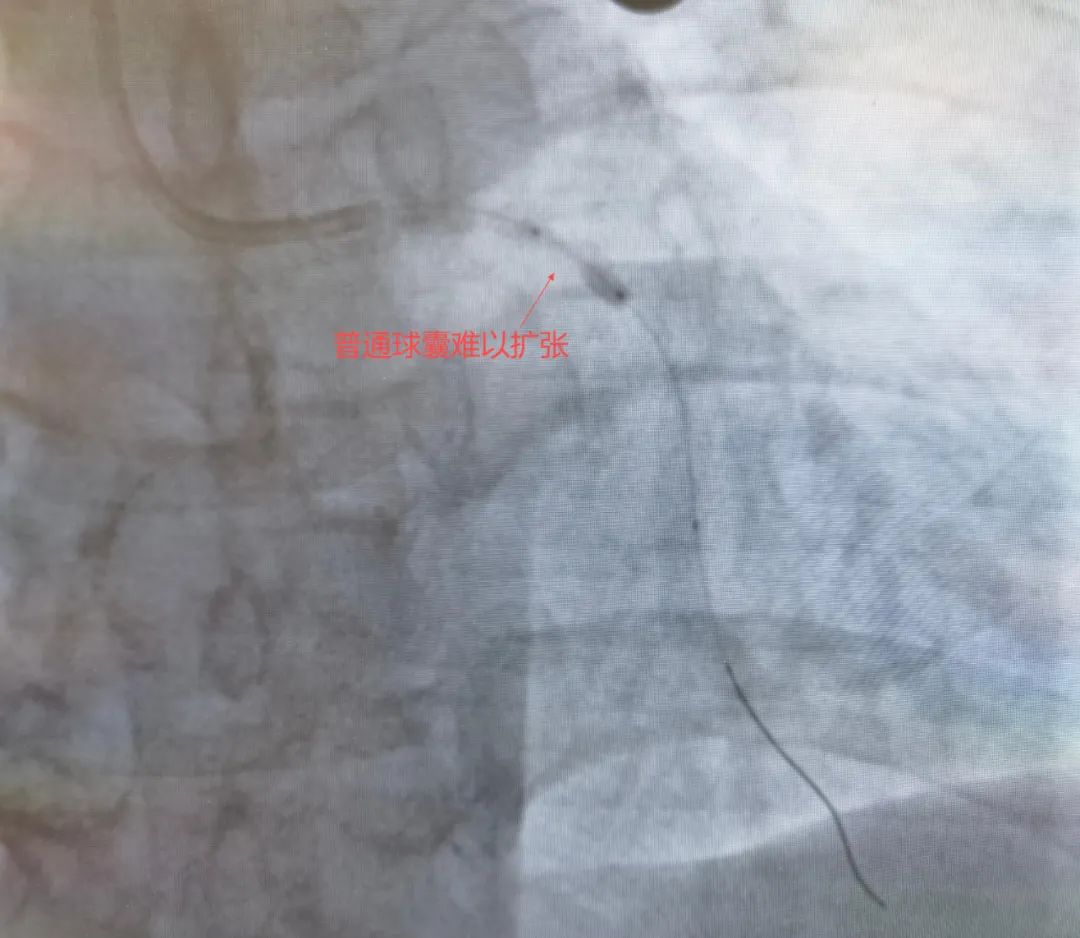

65岁的赵大爷因反复胸闷胸痛入院,冠状动脉造影显示其前降支近段存在重度钙化狭窄,血管钙化程度评分达III级(Nakamura分级),管腔狭窄超过90%。此类病变如同血管内“顽石”,常规介入器械难以通过,传统球囊扩张术无法使血管充分扩张,极易导致夹层等风险,手术难度和风险极高。

针对赵大爷的复杂病情,团队进行了充分术前讨论,决定采用“冠状动脉旋磨+冲击波球囊”的组合方案,最终成功置入支架,整个手术过程顺利,免除了患者外科开胸搭桥的痛苦。